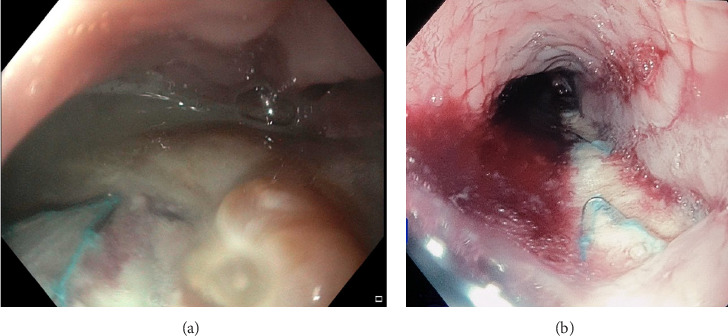

We present a case of an 80-year-old female who presented with chest pain, vomiting and night sweats a few weeks post thoracic endovascular aortic aneurysm repair (TEVAR). A computed tomography (CT) scan demonstrated a type 1B endoleak for which she underwent a repeat TEVAR. Postoperatively, she developed fever, dysphagia, haematemesis and melaena. CT angiography subsequently confirmed an aorto-oesophageal fistula (AEF). Gastroscopy was performed to confirm this and found an ovoid oesophageal perforation with visible aortic graft and purulent fluid. Serial endoscopic oesophageal stents were placed and the patient recovered after an oesophageal Ultraflex stent was placed. Unfortunately, however, the patient was found unresponsive at home with black vomitus and in cardiac arrest and passed away 18 months after her initial endoscopic procedure. This case highlights that AEF is a complication following a TEVAR procedure. This can be managed temporarily with oesophageal stent placement and an Ultraflex stent in the longer term. However, oesophageal stent placement is not curative in cases of significant oesophageal perforation as it does not lead to lead to closure of a large defect.

Abstract Image